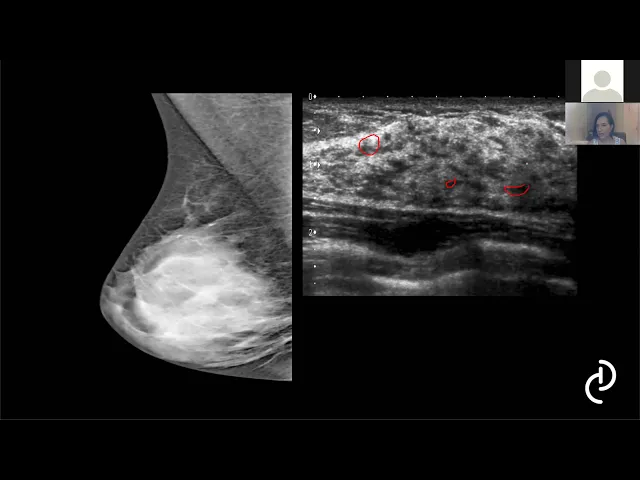

Aula Dra Daniella Prudente: Aprendendo interpretar o BIRADS com casos clínicos.